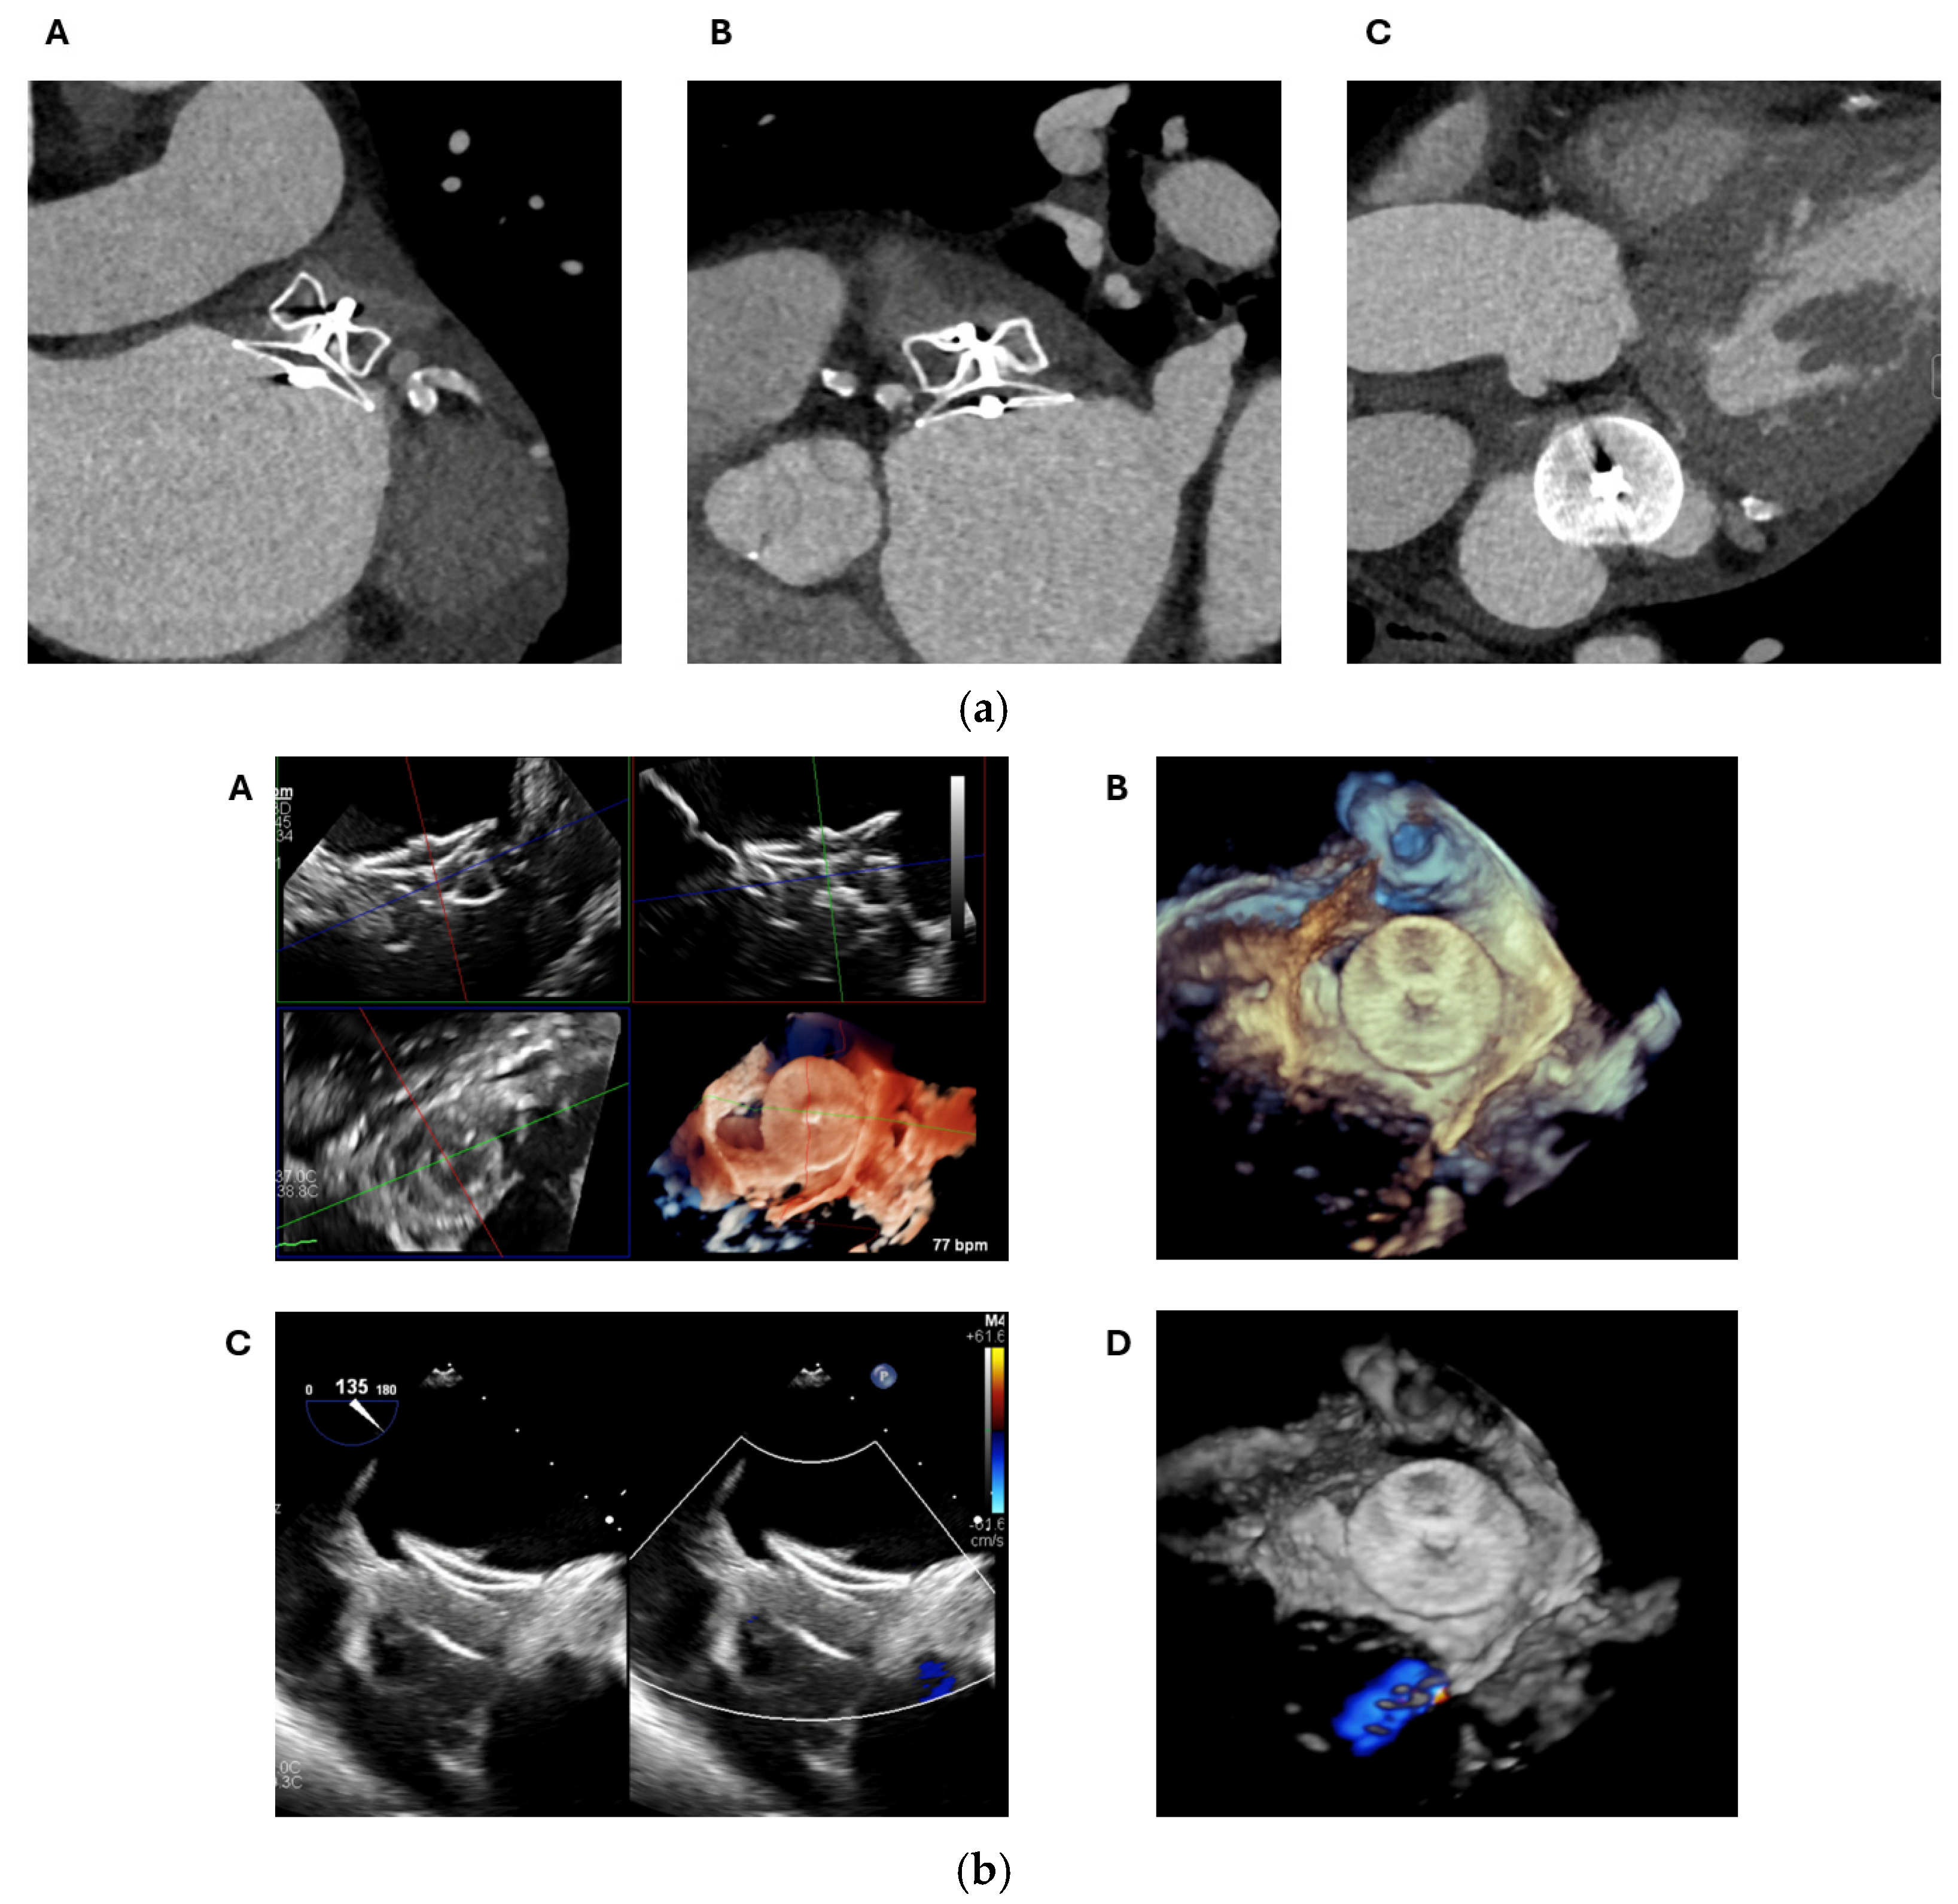

2.1. Cardiac CT

2.1.2. LAA Measurements

2.1.3. Assessment of the Inter-Atrial Septum